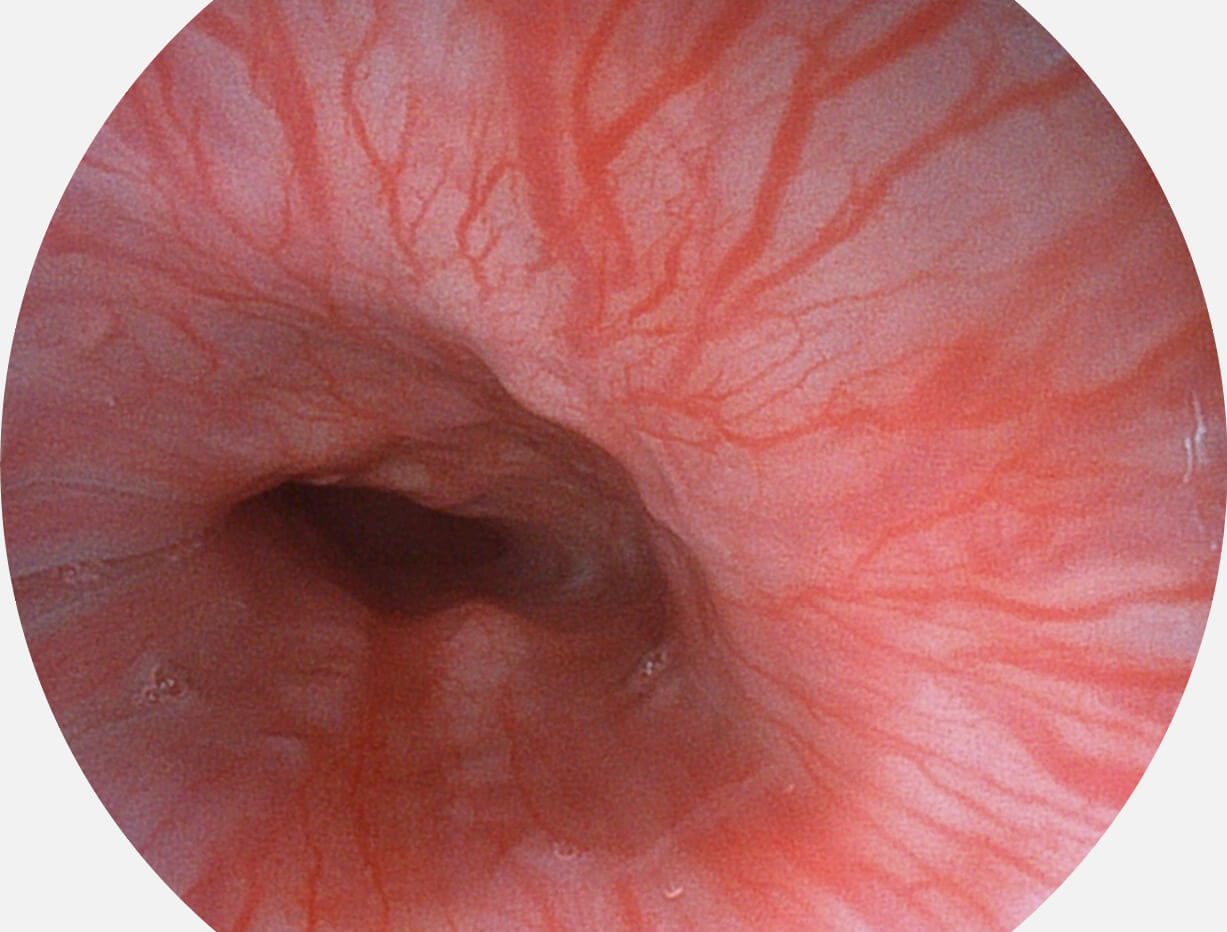

强调浅层黏膜结构的同时,保证照明亮度和提升浅层微血管与中层血管颜色对比度,病变边界更清晰。

VIST图像